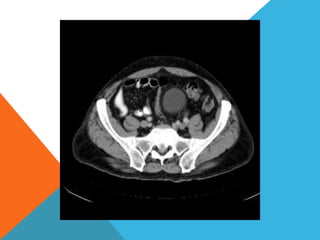

El paciente presentó síntomas de sangrado digestivo y pérdida de peso. Exámenes revelaron gastritis crónica asociada a H. pylori. Un tumor fue descubierto en una colonoscopia normal. La cirugía removió un tumor fibroide solitario, una rara neoplasia mesenquimal que usualmente crece lento y tiene bajo potencial de malignidad. El pronóstico después de la remoción quirúrgica es generalmente bueno.